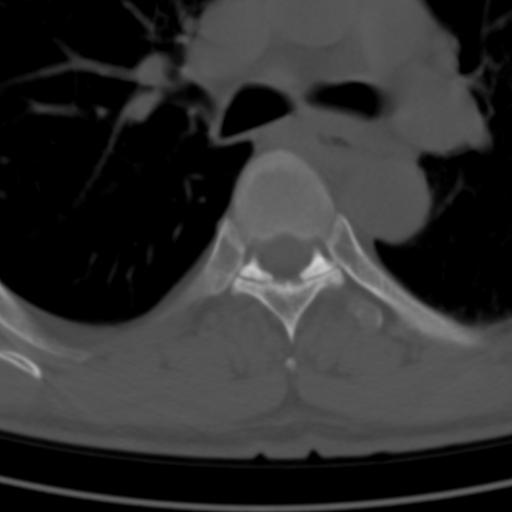

标题: CT25189:胸椎ct,请会诊!

既往食管癌,现行ct检查!

仅见椎体退行性改变

中上段食道癌,椎体轻度退变。

椎体退行性改变,食管癌。

支持中上段食道癌,椎体轻度退变,必要时做ect。

支持中上段食道癌,椎体轻度退变。